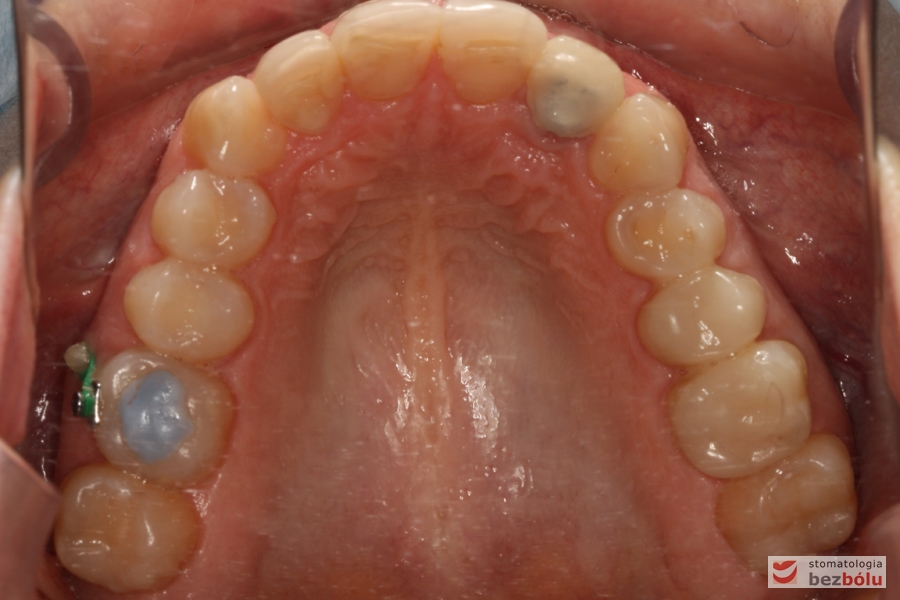

Szczęka - widok okluzyjny, dowargowe i doszczytowe przemieszczenie 6 prawej za pomocą mikrośruby ortodontycznej

Szczęka – widok okluzyjny, dowargowe i doszczytowe przemieszczenie 6 prawej za pomocą mikrośruby ortodontycznej